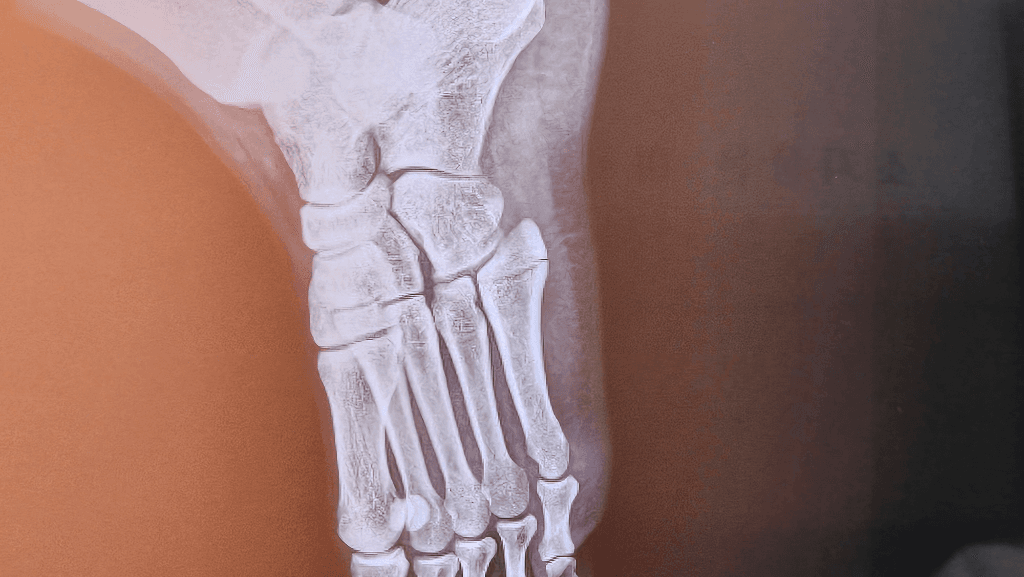

두번째 사진을 보면 중족골 base에 골절선이 길게 이어져 있는 것을 확인할 수 있습니다

첫번 째 사진보다는 훨씬 뚜렷하게 보이는 것 같습니다